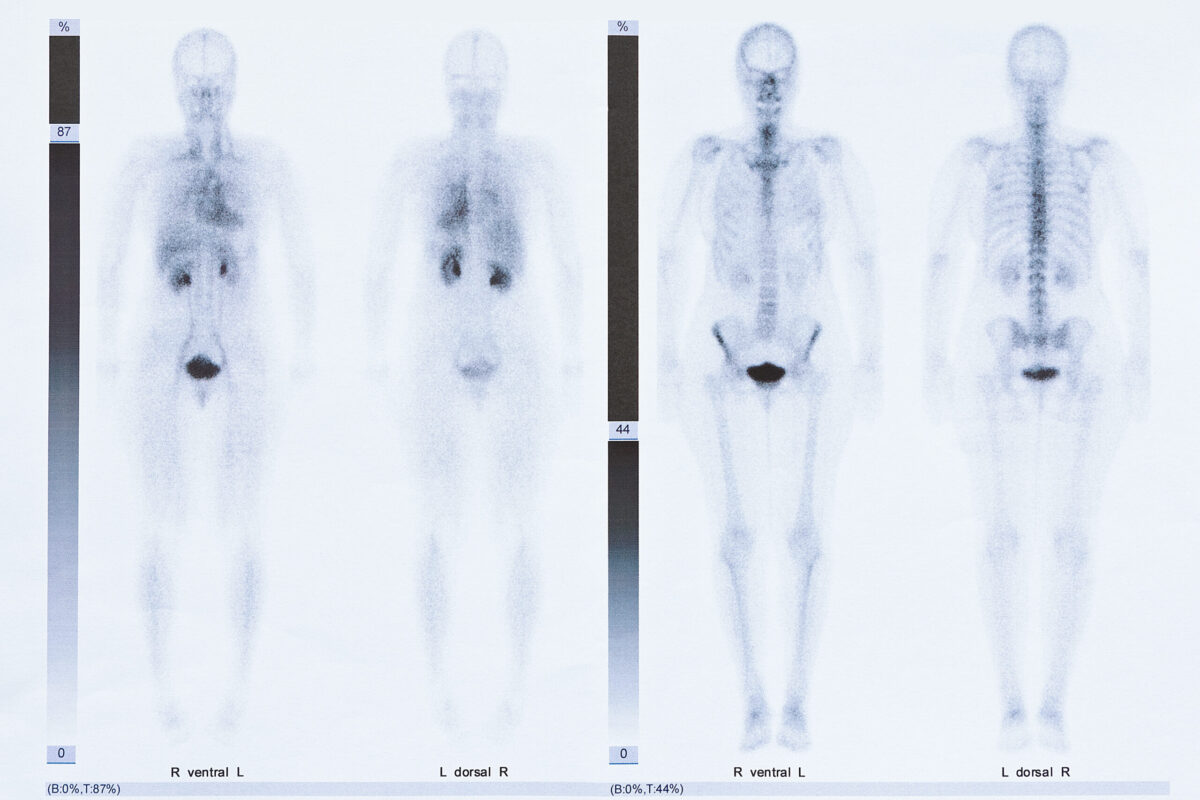

Continuing our series, this month we discuss bone scans, how they are used for MBC, and how to find trials studying bone scans for people with MBC.